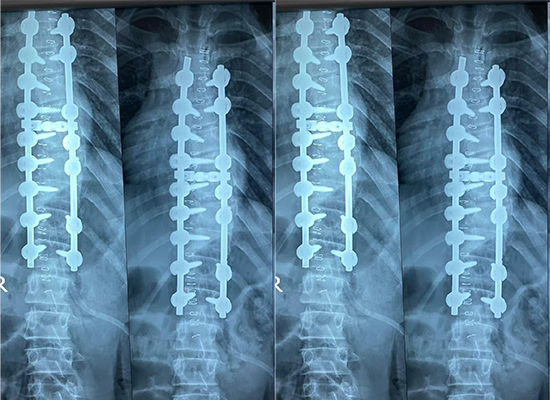

O cogo la, sɔgɔsɔgɔninjɛ latilenni fɛɛrɛ dɔ kɛra ka ɲɛ sigida la kolotugudaw dɔgɔtɔrɔso dɔ la Daka, Bangaladeshi , o kɛra banabagatɔ muso dɔ ye min si ye san 14 ye, a sɔrɔla ko sɔgɔsɔgɔninjɛ bɛ a la funankɛninw na. Opereli kun tun ye ka kɔkolo sɔgɔsɔgɔninjɛ latilen, ka a labɛncogo segin a cogo kɔrɔ la, ani ka kɔnɔna jɔli sabatilen sɔrɔ ni 6,0mm pedicle screw–rod system ye.

Nin sɔgɔsɔgɔninjɛ latilenni fɛɛrɛ in kama, 6,0mm pedicle screw system sugandira ka kɛ fixation solution fɔlɔ ye. Pedicle screw–rod constructs bɛ kɛ ka caya kɔkolo tiɲɛni opereli la ka da u seko kan ka kɔkolo jɔli barikama di ani ka kɔkolo labɛncogo kɔlɔsi tigitigi.

Opereli kɔfɛ ja minnu kɛra, olu y’a jira ko kɔkolo labɛncogo ka ɲi ni i ye a suma ni a cogoya ye sani opereli ka kɛ. Fixation construct (fixation construct) tun bɛ i n’a fɔ a sabatilen don, ka dɛmɛ don latilenni laɲininen na. Opereli jɛkulu ka fɔ la, banabagatɔ ye kɛnɛya sɔrɔ opereli kɔfɛ min bɛ a wasa, gɛlɛya si ma sɔrɔ teliya la min bɛ tali kɛ fiɲɛ bilali la.

Nin sɔgɔsɔgɔninjɛ latilenni ko in min bɔra Daka, Bangaladeshi jamana na, o bɛ kɛcogo jira 6,0mm pedicle screw system kɛnɛyaso la funankɛninw ka kɔkolo tiɲɛni opereli la. Nin ko in bɛ fɛn kolomaw jira i n’a fɔ segin-ka-bɔnyew, deformité correction contrôlée, ani opereli kɔfɛ ɲɔgɔndan sabatili.

Kɔkolo labɛncogo jateminɛna ni ja lajɛw ye sani opereli ka kɛ ani opereli kɔfɛ jateminɛw ye minnu kɛra ni rezow ye walasa ka latilenni ni a sirili sabatili dafa.

Opereli kɔfɛ ja minnu kɛra, olu y’a jira ko kɔkolo labɛncogo ɲɛna, wa banabagatɔ y’a jira ko a kɛnɛyara ka ɲɛ ni kɔnɔna jɔli sabatilen ye.